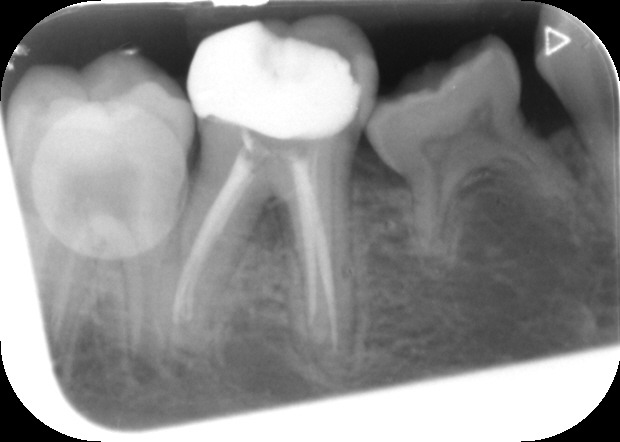

Files of different sizes are used to eliminate bacteria and infection and to shape the canals. The canals are disinfected thoroughly with irrigants and later the canals will be sealed in 3 dimensions with a special medicament called gutta-percha to prevent reinfection of the tooth and the access cavity will be sealed with a temporary filling.

After a few weeks, the tooth will be checked and when all the infection has cleared, a crown will be usually required to protect the restore the tooth to function.